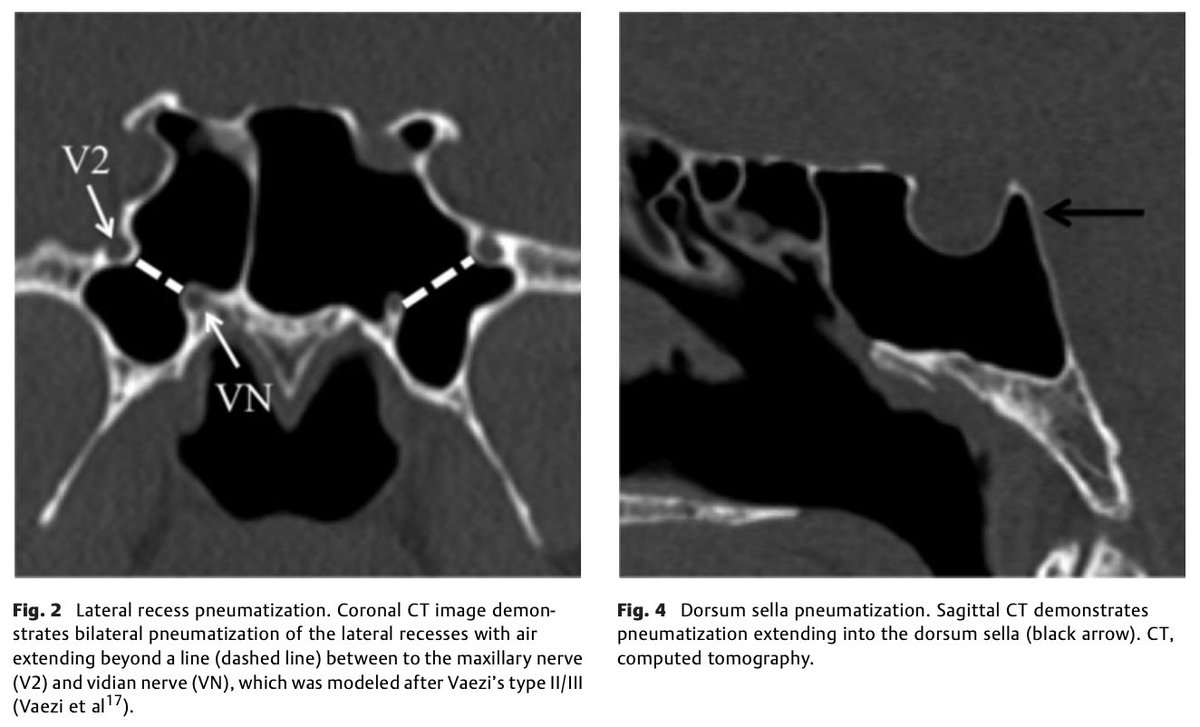

#JNLSB_Online Preoperative Computed Tomography Imaging of the Sphenoid Sinus: Striving Towards Safe Transsphenoidal Surgery#ENT#EEA#transsphenoidal#nsgy#safety#pituitary#approaches#neurorads#neuroanatomy https://www.thieme-connect.de/products/ejournals/html/10.1055/s-0039-1691831 … pic.twitter.com/c3kwPntykW